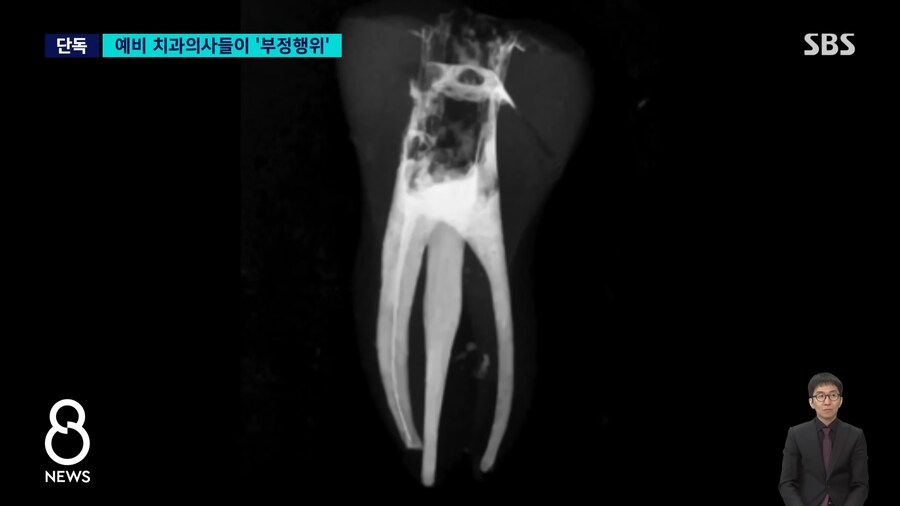

저기 구멍뚫린것 처럼 보이는 검은색이 신경치료하면서 충전제를

꼼꼼히 채워넣지 못한 부분..

(실제 교수지도 하에 사람 치료)

수정 : 실제 저 실습이 사람에게 행해졌는지는 알려지지 않고

해당 학생들이 실제로 교수지도하에 사람들을 진료하는 신분이라고 함